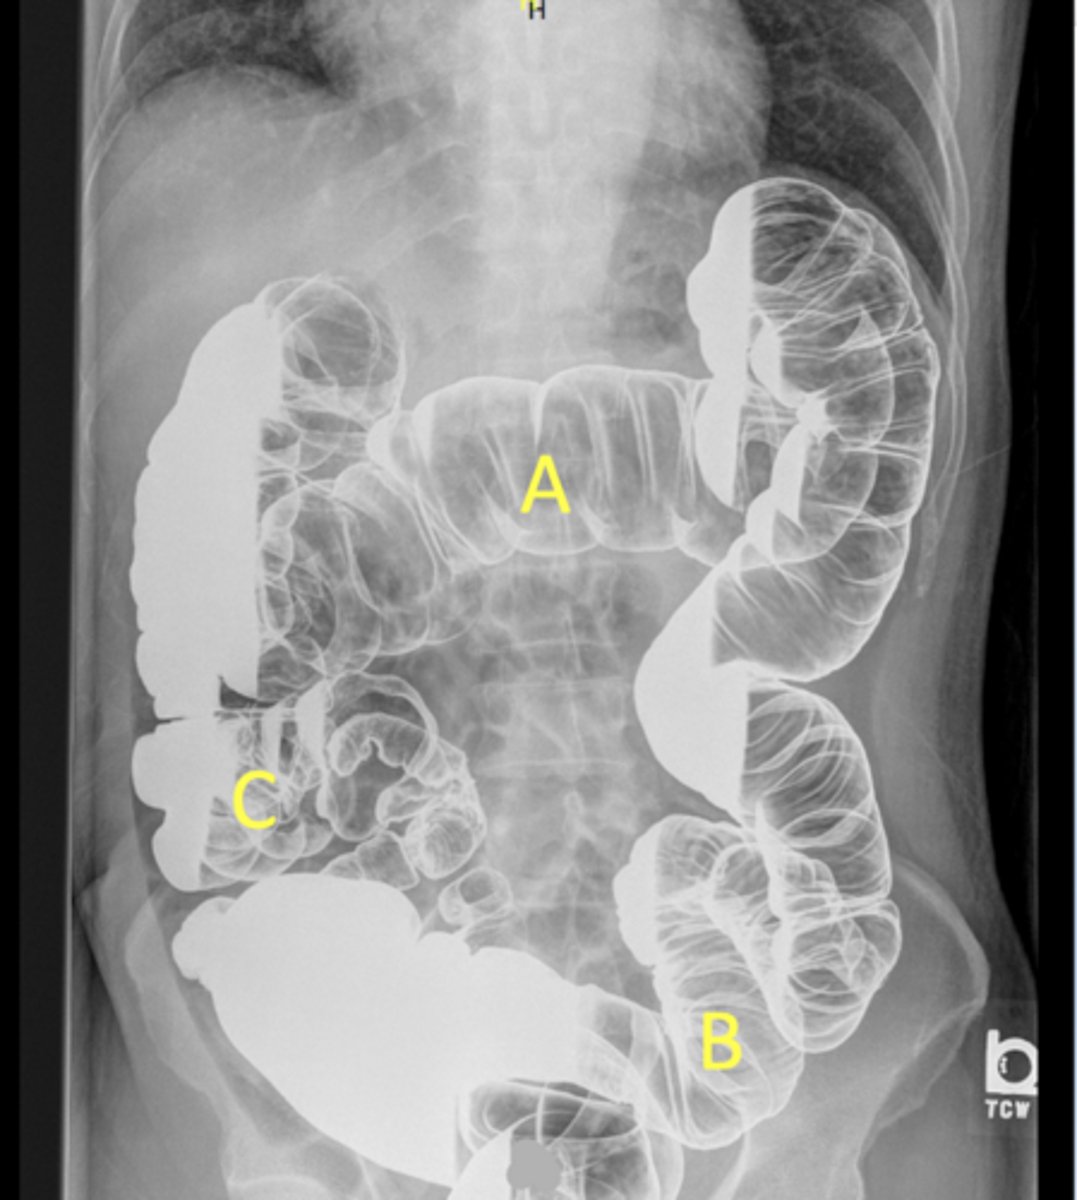

A - Transverse colon

B - Sigmoid colon

C - Cecum/ascending colon/iliocecal junction

pt is on their side due to seeing white fluid and haustra

Label the radiograph